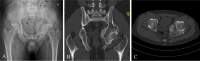

Results: The mean follow-up time was 35.3 months (range 28-45 months). There was no intraoperative complication. Negative surgical margins were achieved in all patients. Postoperative pelvic radiographs showed that 3DPIs matched the shape and size of the bone defect. The anterior-posterior, inlet, and outlet pelvic radiograph demonstrated precise reconstruction consistent with the surgical planning. In addition, tomosynthesis-Shimadzu metal artifact reduction technology (T-SMART) showed good osseointegration at an average of three months after surgery (range 2-4 months). There was no local recurrence or tumor metastasis. The average MSTS score was 24.4 (range 23-27) at the last follow-up. Delayed wound healing was observed in one patient, and the wounds healed after debridement. Prosthesis-related complications were not detected during the follow-up, such as aseptic loosening or structure failure.